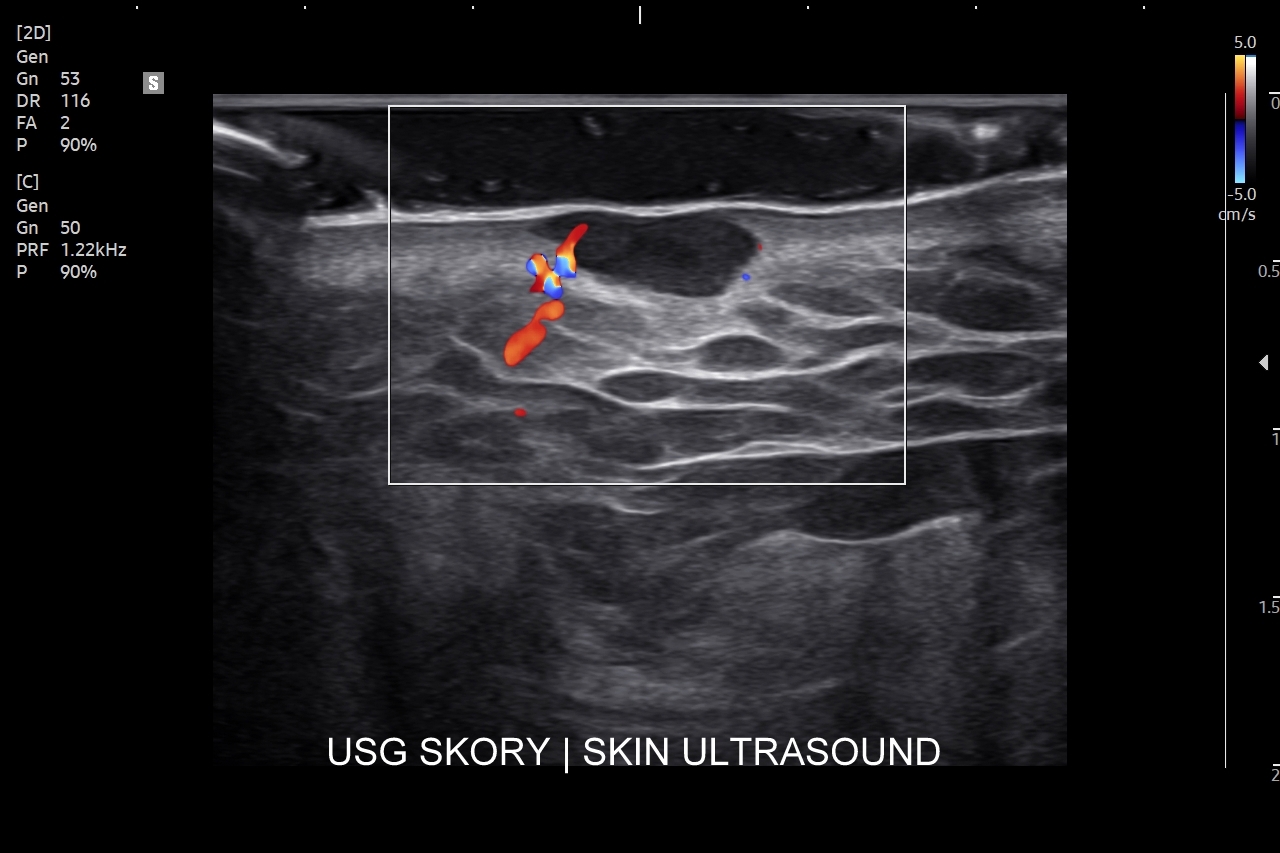

Badanie USG skóry i powłok jest metodą diagnostyczną, która swoją czułością oraz dokładnością przewyższa w ocenie patologii powłok badanie rezonansem magnetycznym. W obrębie powłok ciała w badaniu USG najczęściej rozpoznaje się różnorodne guzy oraz stany zapalne. Wśród guzów dominują łagodne tłuszczaki, kaszaki i torbiele inkluzyjne, a także przepukliny. U młodszych pacjentów często wykrywa się naczyniaki. Rzadziej spotkane są guzy złośliwe jak mięsaki, czy przerzuty nowotworowe. W pracowni USG dr Szczepańskiego poza wizualną oceną guzów powłok przeprowadzana jest ich ocena biologii w kontekście cech złośliwości i oceny przewidywalnego tempa wzrostu.

W obrębie schorzeń zapalnych typowo wykrywa się ropnie, przetoki, infekcyjne zapalenia tkanki podskórnej (np. róża), rzadziej głębsze infekcje powięzi i zagrażające życiu infekcje podpowięziowe. Badanie USG powłok jest bardzo przydatne w chirurgii, gdyż dzięki niemu można szybko i sprawnie zdiagnozować powikłania chirurgiczne takie jak krwiaki, zacieki, ropnie, ciała obce, przepukliny brzuszne, a także można oceniać i monitorować gojenie się blizny, czy położenie drenów. USG pomaga także diagnozować endometriozę w powłokach brzucha i w bliznach po cięciu cesarskim.

Badanie USG twarzy, często nie do końca fortunnie zwane USG skóry twarzy, to stosunkowo nowa metoda diagnostyczna wprowadzona we Wrocławiu do użytku przez dr Tomasza Szczepańskiego, a wykonywana w przypadku schorzeń z zakresu medycyny estetycznej, dermatologii, laryngologii, stomatologii i chirurgii. Wśród rozpoznań w badaniu USG skóry twarzy dominują choroby infekcyjne takie jak rozprzestrzeniające się w tkankach miękkich zapalenia i ropowice pochodzące od zapaleń zębów czy migdałków, powikłania ropne w przebiegu trądziku pospolitego lub różowatego, po iniekcjach wypełniaczy i po innych zabiegach z zakresu medycyny estetycznej. Kolejną dużą grupą patologii skóry twarzy są torbiele inkluzyjne, których przykładem są kaszaki, oraz guzy twarzy, wśród których dominują ziarniniaki jako odległe acz częste powikłanie depozycji wypełniaczy z kwasu hialuronowego.

Aparatura do USG skóry

Pracownia dr Tomasza Szczepańskiego świadcząca usługę USG skóry we Wrocławiu, jako jedna z kilku w Polsce, wyposażona jest w aparaturę dysponującą zaawansowaną technologią, oprogramowaniem oraz specjalistycznymi sondami umożliwiającymi obrazowanie skóry o niestandardowo wysokiej rozdzielczości, a także diagnostykę funkcjonalną i biologiczną zmian chorobowych w skórze oraz w powłokach ciała.